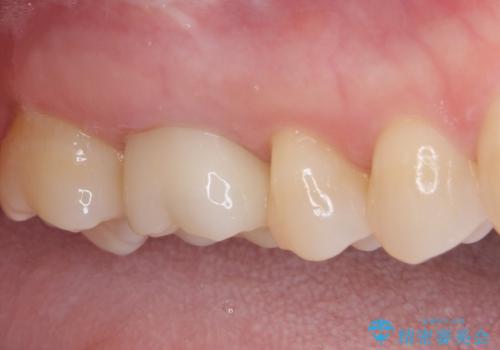

- 上下の奥歯に違和感を感じ、近医にて虫歯を指摘されたとのことで来院された患者様です。

診査したところ、下顎の奥歯は膿の出口ができており、上顎の奥歯は噛んだときに痛みを感じている状態でした。

まずは根管治療を行い、症状が落ち着いたことを確認して、オールセラミッククラウンにて補綴治療を行うこととしました。

処置後、下顎の膿の出口はすぐに消えましたが、レントゲン写真からも分かるとおり、歯根途中に穴が開いており、充填材が歯根外にはみ出していました。数ヶ月経過を見たところ、特に異常は認められなかったため、補綴治療を行いました。